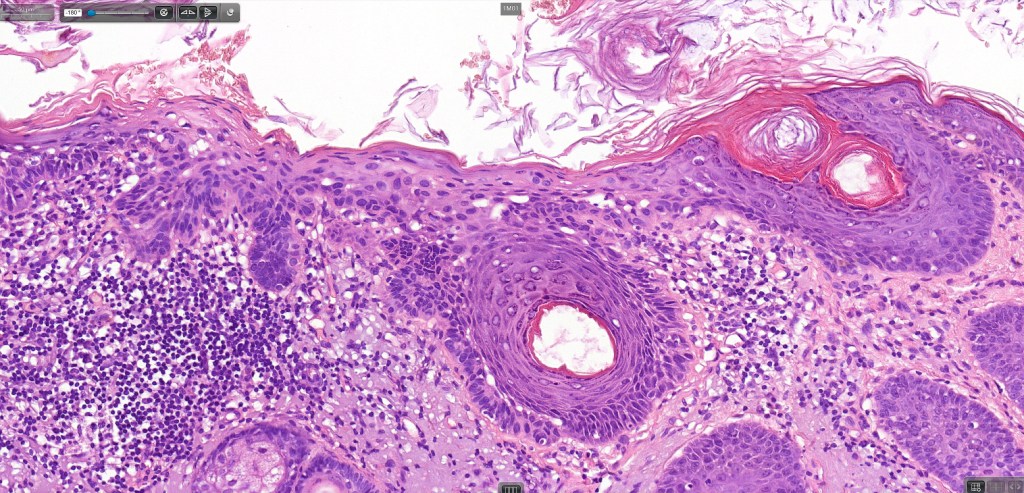

•Hyperkeratotic/hyperplastic actinic keratosis represents the prototype-alternating hyperkeratosis & parakeratosis- the former overlies the follicular & sweat duct ostia (Freudenthal funnel) while the latter overlies the interadnexal dysplastic epithelium & ranges from basal cell layer though to full thickness dysplasia (Bowenoid actinic keratosis); budding from the epidermis is a common finding; dysplastic epithelium commonly forms a mantle around the follicles and superficial sweat ducts

•Variable lack of maturation, nuclear irregularity, pleomorphism & mitotic activity

•Solar elastosis

.Superficial dermal lymphohistiocytic infiltrate